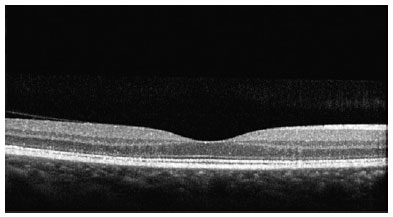

In the pre-macula stage, spectral domain optical coherence tomography (SD-OCT) can detect alterations in the photoreceptor layer, at the junction of the internal and external segments of the retina (ISOS), and in the retinal pigment epithelium (RPE). It is possible to identify discrete irregularities in the bilateral perifoveal region. In the initial phase of TR, small faults can be detected in the photoreceptor layers, ISOS, and RPE in the perifoveal region in addition to the above irregularities.

SD-OCT was useful for the classification of TR. Of the nine patients with TR caused by antimalarials, 44% (4) presented premacular maculopathy (Figure 1), 22% (2) at the initial stage (Figure 2), 22% (2) at the moderate stage (Figure 3), 11% (1) at the advanced stage (Figure 4), and none at the terminal stage (Table 3).